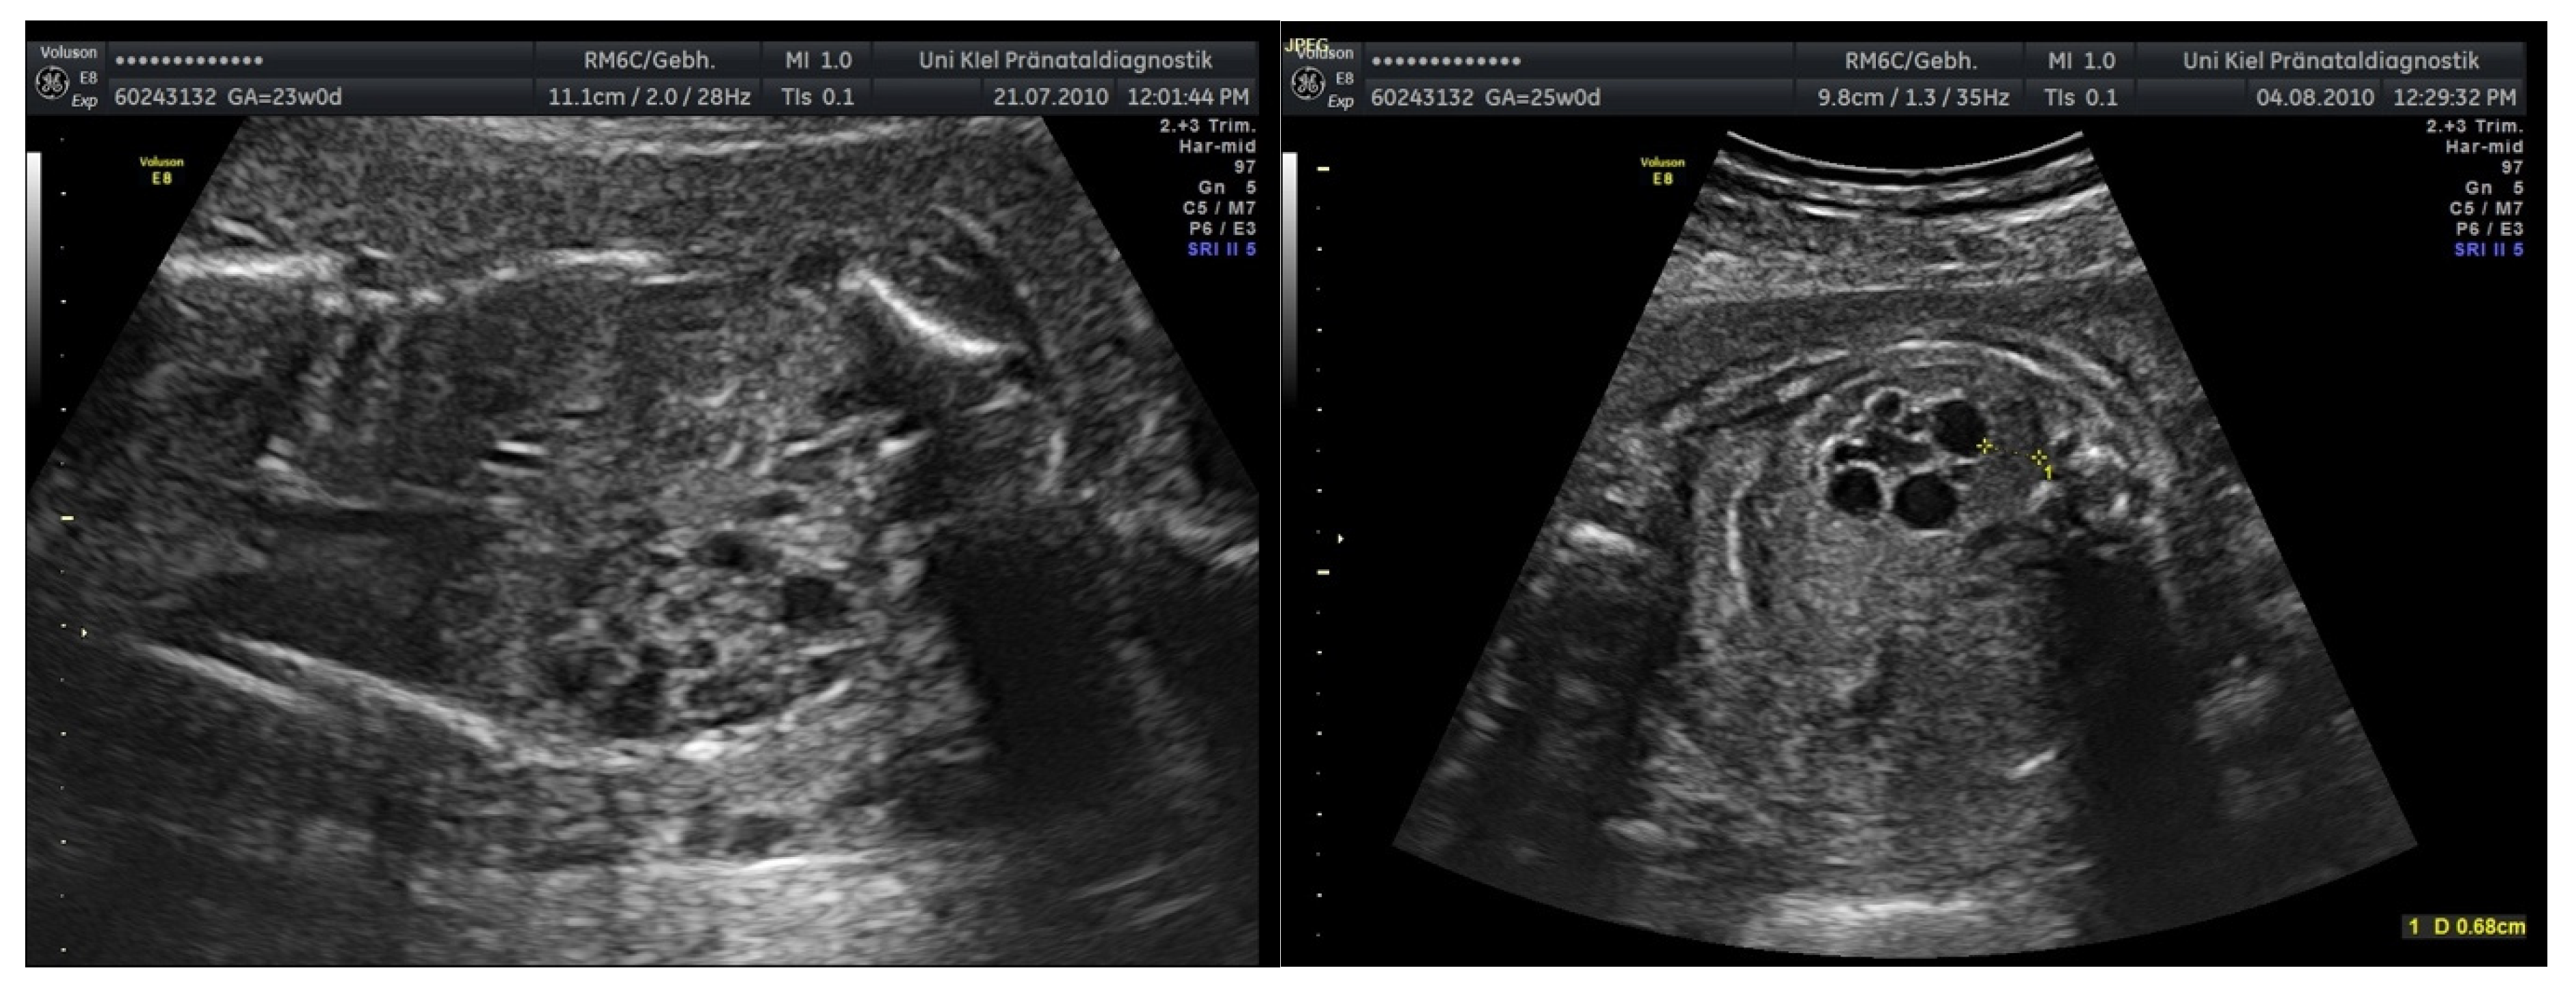

3.3.4. Chromosomal Aberrations and Severe Malformations

4.5. Urogenital Malformations and Chromosomal Abnormalities